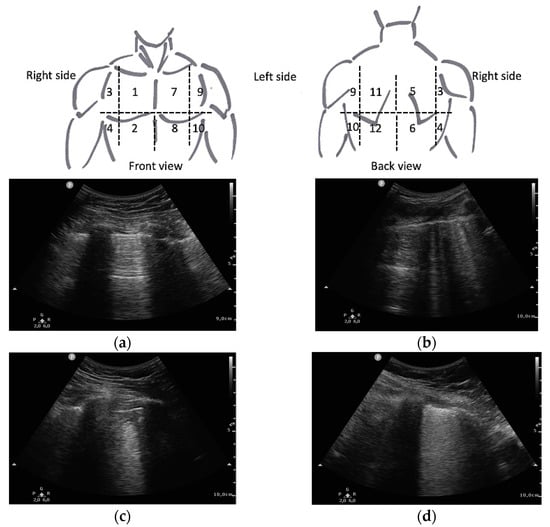

- Soldati, G.; Smargiassi, A.; Inchingolo, R.; Buonsenso, D.; Perrone, T.; Briganti, D.F.; Perlini, S.; Torri, E.; Mariani, A.; Mossolani, E.E.; et al. Proposal for International Standardization of the Use of Lung Ultrasound for Patients with COVID-19. J. Ultrasound Med. 2020, 39, 1413–1419. [Google Scholar] [CrossRef] [PubMed]

- Mento, F.; Perrone, T.; Macioce, V.N.; Tursi, F.; Buonsenso, D.; Torri, E.; Smargiassi, A.; Inchingolo, R.; Soldati, G.; Demi, L. On the Impact of Different Lung Ultrasound Imaging Protocols in the Evaluation of Patients Affected by Coronavirus Disease 2019. J. Ultrasound Med. 2021, 40, 2235–2238. [Google Scholar] [CrossRef]